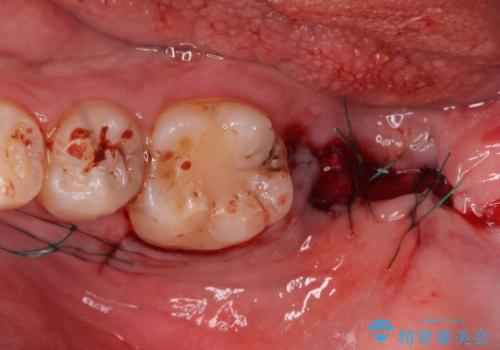

その後、インプラント治療、セラミック治療を行いました。

一度治療するはを全て仮歯に変えて、歯茎を整えてからセラミックを装着しました。

また、虫歯が歯肉の中まである場合はAPF(歯肉弁根尖側移動術)も行なっています。